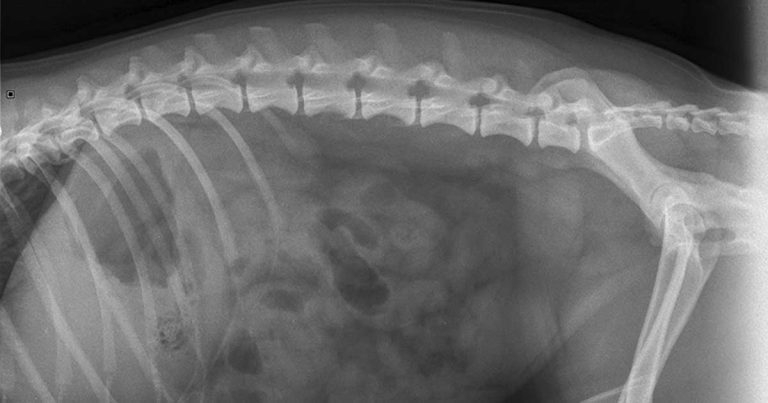

Radiographs are complementary and, if ultrasound isn’t available, can allow assessment for organomegaly, free fluid and indications of gastrointestinal foreign body.

Abdominal radiographs showed some irregular gas in the intestines and a suspected fabric density foreign body (Figures 5 to 7).